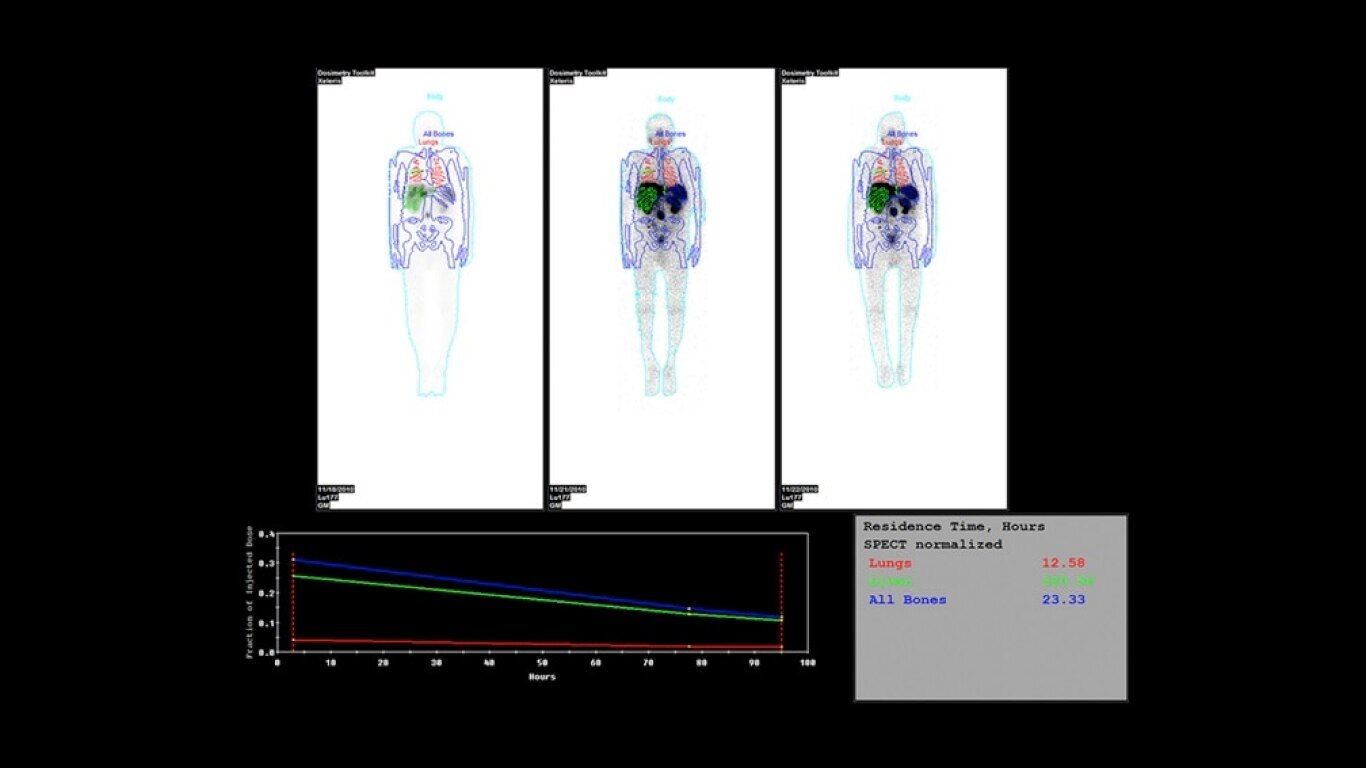

Experience a new productivity hub for hybrid imaging. By automating SPECT/CT reconstruction, SmartConsole simplifies the workflow for complex hybrid and quantitative protocols and allows technologists to review results directly at the scanner console. It also allows physicians to review scans remotely from mobile devices. They can modify processing settings and initiate study processing anytime, anywhere across a LAN or a WAN*.

SmartConsole enables a noticeable improvement in productivity. Now, a physician can provide their input remotely and digitally. For example, physicians can review a whole-body bone scan directly on their tablet or other mobile device and define the scan range limits they need from wherever they are. The time saved with this switch to a digital workflow helps make it possible to complete exams in predictable time slots.